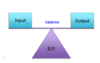

The kidneys help to maintain _________ in the body by controlling the composition of the ECF

homeostasis

What are 5 inputs into the kidney? How is it produced?

- Ingestion

- Inhalation

- Absorption through body surfaces

- Injection

- Produced through metabolism

What are 4 outputs into the kidney? How are they consumed?

- Kidneys

- Lungs

- Digestive tract

- Body surface (sweat, tears)

- Consumed through metabolism